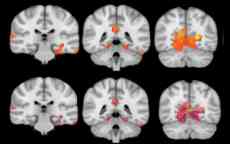

Swinburne research has found low-level cannabis use in adolescents may have an effect on the amount of grey matter volume found in their brains.

In a first-of-its-kind study, Swinburne cognitive neuroscience lecturer, Dr Catherine Orr, compared the grey matter volume in a group of 46 14-year-olds who had only used cannabis once or twice with a control group of teens who had never used the drug.

The research, completed with Professor Hugh Garavan at the University of Vermont in the US, has shown that teens who used cannabis just once or twice have more grey matter volume than their cannabis-naïve counterparts.